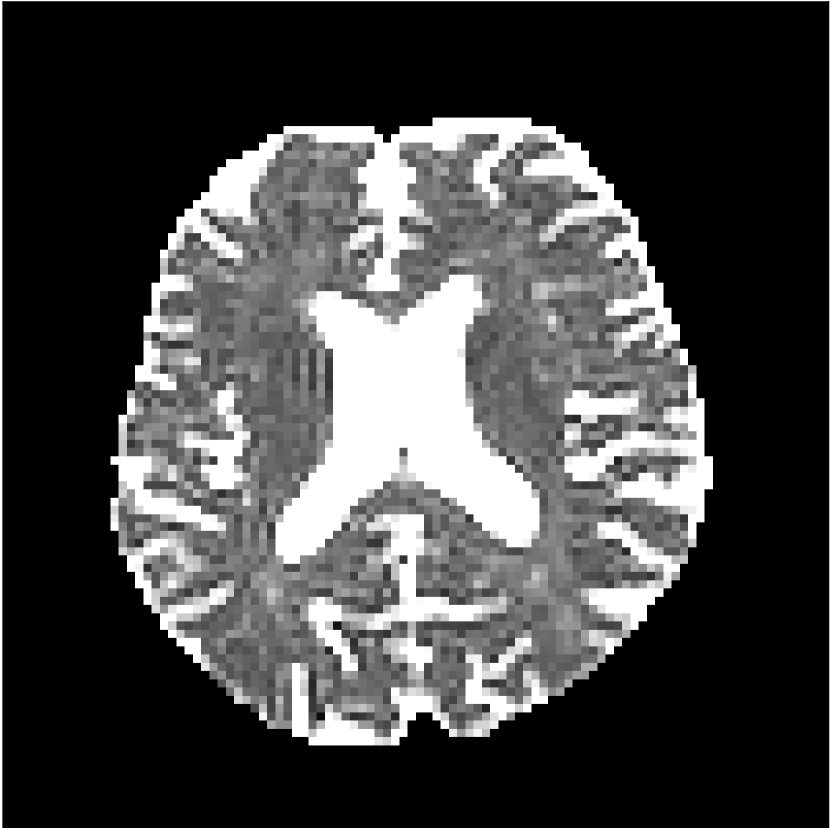

Figure 8 shows examples of non-diffusion-weighted images before and after processing. The raw images (Raw) served as the input for the magnitude deep learning (MCNN) and complex deep learning (CCNN) methods.

Raw

MCNN,

MCNN Resid.,

CCNN,

CCNN Resid.,

No PF

5/8 PF

Both methods remove artifacts, but the MCNN method allows residual rippling artifacts to pass through in the presence of partial Fourier. These rippling artifacts are not present in the CCNN method.